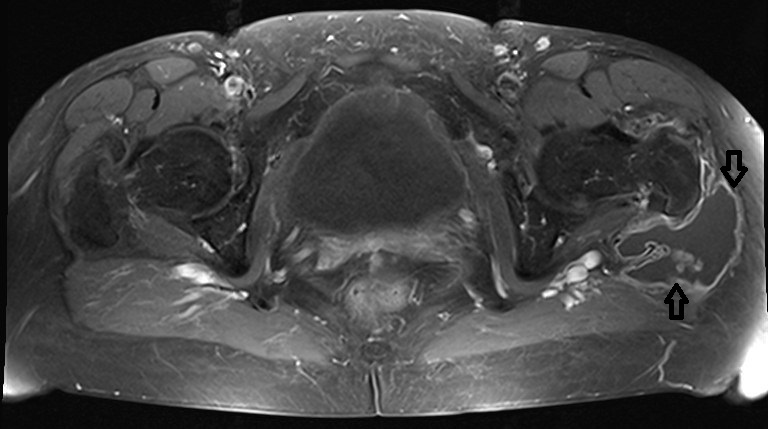

Lateral to the greater trochanter in the bursa trochanterica there was evidence of fluid showing homogeneous hyperintensity without sedimentation in fluid-sensitive sequences. Proton-weighted imaging revealed two nodular wall extensions in teardrop shape extending craniolaterally. These extensions measured a maximum of 1 cm at the base. In addition, at the roof of the fluid-filled cavity there was a space measuring approximately 1.5 x 0.5 cm. In the native fat-suppressed T1 turbospinecho sequence, this space-occupying lesion was partially hyperintense. This was considered to be hemosiderin. After application of gadolinium, there was a vigorous enhancement of the lining of the height. In addition, there was diffuse enhancement of the muscles in the immediate vicinity of the bursa. The hemorrhaged mass showed no enhancement of the contrast medium. In summary, the recent MRI exhibited an enlarged trochanteric bursitis with some intrabursal soft tissue formation suspicious for pigmented villo-nodular synovitis (PVNS) of the bursa trochanteric (PVNSBT) (Figure 1 [Fig. 1], Figure 2 [Fig. 2], Figure 3 [Fig. 3], Figure 4 [Fig. 4]).

Figure 2: Proton-weighted transversal plane exhibiting the enlargd bursa filled with fluid and soft-tissue protruded into the bursa trochanterica (marked by an arrow)